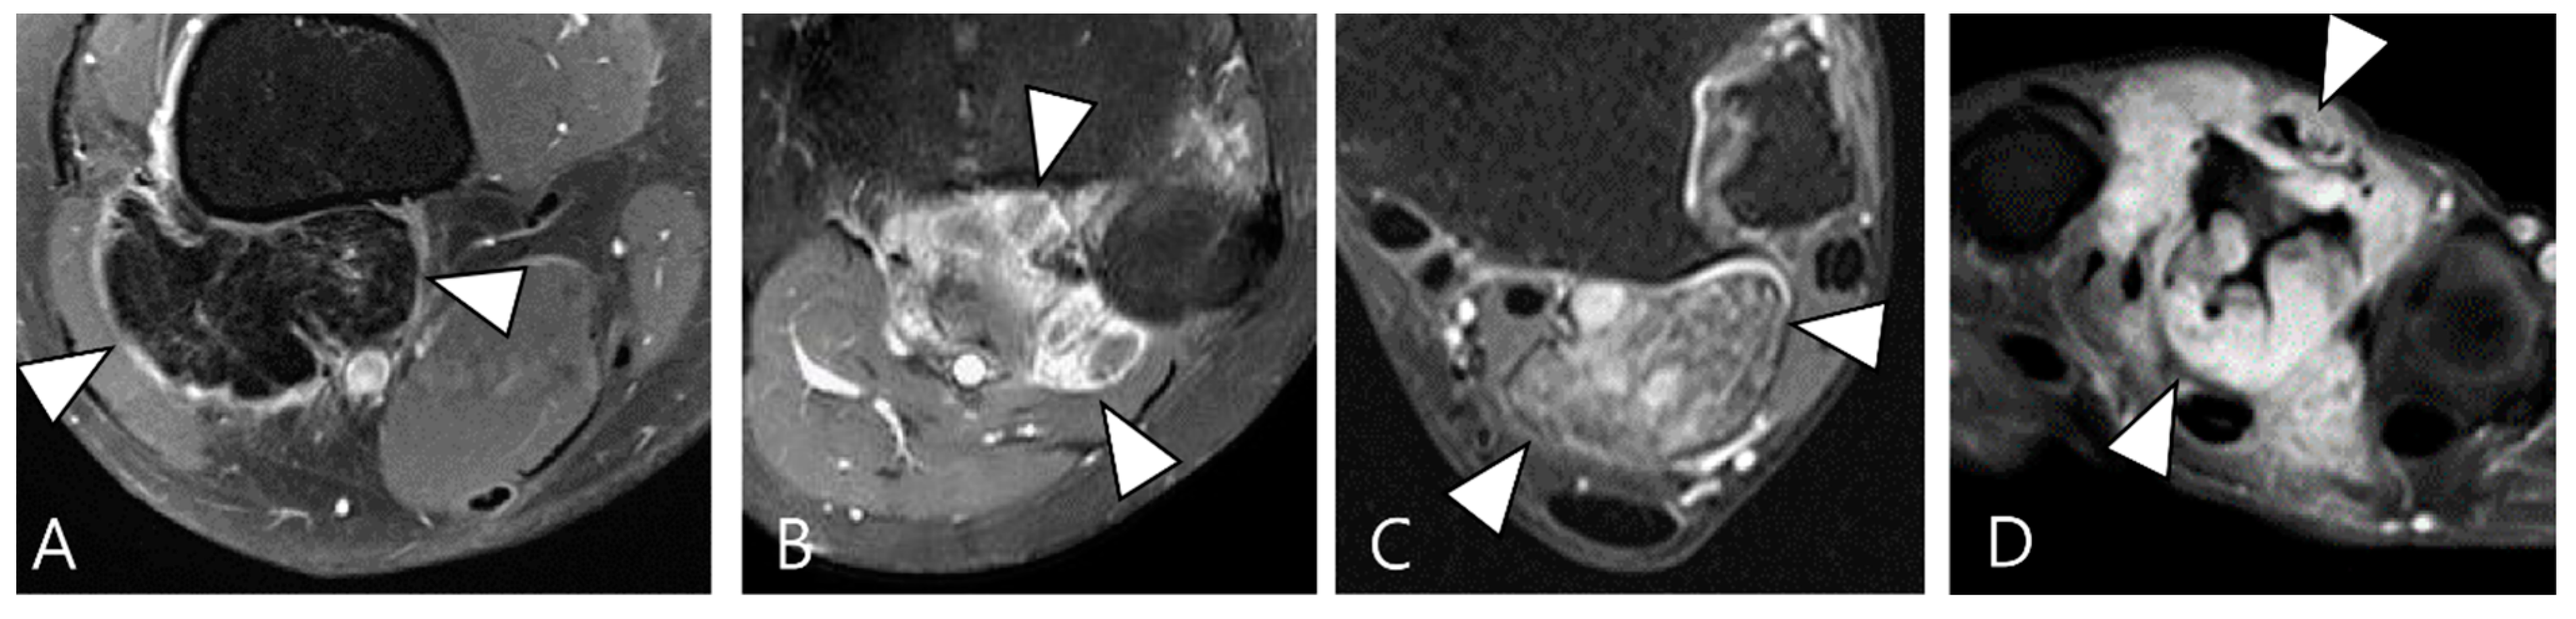

Figure 2.

Enhancement patterns of pathology-proven D-TSCGT. (A) No contrast enhancement within the lobulated mass (arrowheads) in the posterior knee. (B) Peripheral contrast enhancement of the mass with a sparing central portion (arrowheads) in the posterior knee. (C) Heterogenous contrast enhancement of the mass (arrowheads) in the posterior ankle. (D) Homogenous contrast enhancement of the mass (arrowheads) surrounding the third metacarpal bone.